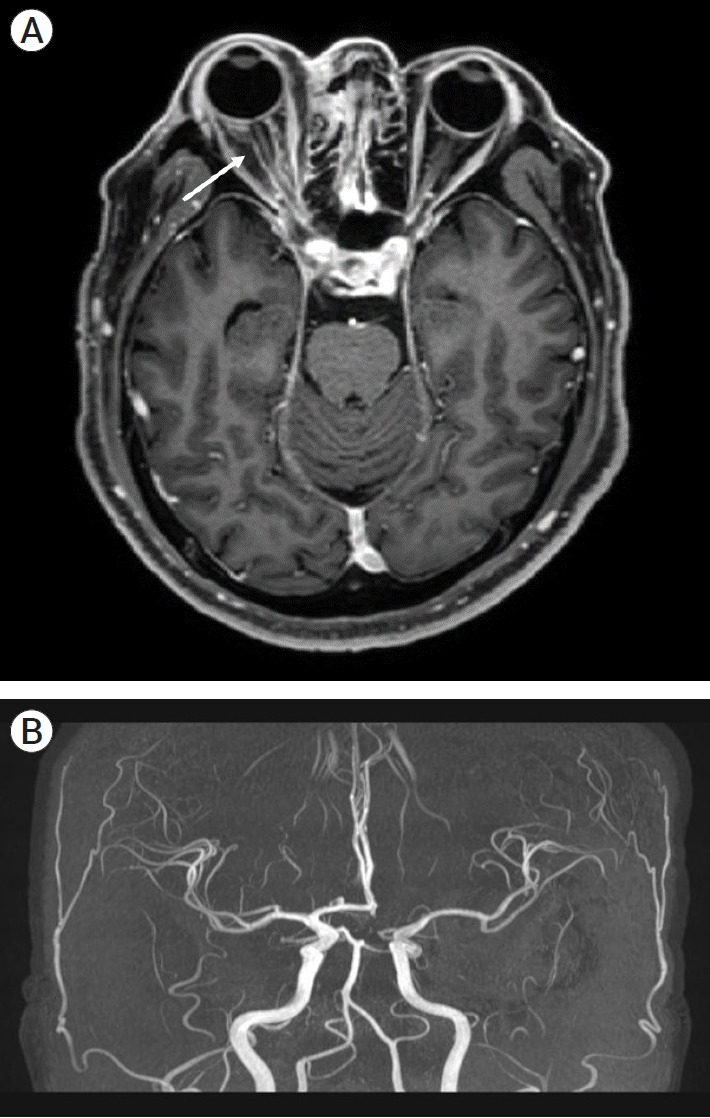

中枢神经系统(CNS)曲霉病是一种危及生命的感染,主要影响免疫功能低下患者,并可能通过血管侵入导致严重的脑梗死。然而,关于曲霉病诱发的脑梗死的治疗选择的数据有限,特别是手术治疗,如颞浅动脉(STA)-大脑中动脉(MCA)搭桥手术。在此,我们报告一个59岁男性右眼进行性上睑下垂的脑梗死病例。具体来说,他有同侧MCA狭窄,起源于侵袭性曲霉菌病引起的鼻窦炎。3个月后,患者因脑梗死恶化和颈内动脉完全闭塞再次入院。保守治疗未能改善脑灌注,导致神经功能逐渐衰退。因此,行STA-MCA搭桥以稳定患者。术后影像学显示通畅的旁路移植术和增强的脑灌注。虽然患者经历了持续的左侧偏瘫,但他的整体神经系统状况保持稳定1年,格拉斯哥昏迷评分为15分。对于曲霉菌病引起的血管炎导致脑梗死继发于ICA全闭塞的患者,STA-MCA旁路治疗应被视为一种潜在的治疗选择。

Central nervous system (CNS) aspergillosis is a life-threatening infection primarily affecting immunocompromised patients and may lead to severe cerebral infarction through vascular invasion. However, there is limited data on the treatment options for aspergillosis-induced cerebral infarction especially surgical treatments such as superficial temporal artery (STA)-middle cerebral artery (MCA) bypass surgery. Herein, we present a case of cerebral infarction in a 59-year-old male with progressive right eye ptosis. Specifically, he had ipsilateral MCA stenosis originating from paranasal sinusitis due to invasive aspergillosis. After 3 months, the patient was readmitted due to worsening cerebral infarction and complete internal carotid artery (ICA) occlusion. Conservative treatment failed to improve cerebral perfusion, leading to gradual neurological decline. Consequently, STA-MCA bypass was performed to stabilise the patient. Postoperative imaging revealed a patent bypass graft and an enhanced cerebral perfusion. Although the patient experienced persistent left-sided hemiparesis, his overall neurological condition remained stable for 1 year, with a Glasgow Coma Scale score of 15. STA-MCA bypass should be considered a potential treatment option for patients with aspergillosis-induced vasculitis resulting in cerebral infarction secondary to total ICA occlusion.